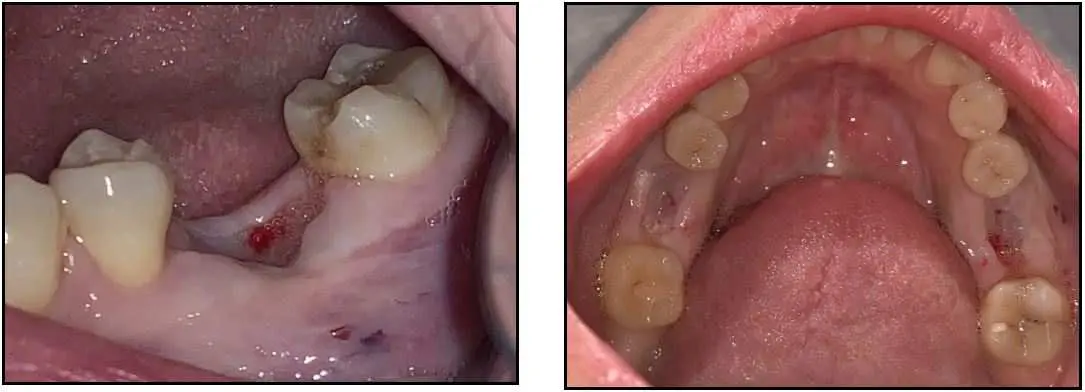

ZERAMEX® XT Case Report

This case documents a delayed placement of 2 ZERAMEX XT 5.5x10mm implants followed by immediate fixture level impressions and placement of healing caps. The patient traveled 2.5 hours to my office 4 weeks prior for removal of #19 and #30 with diagnosis of non-restorable and failed root canals. The teeth were extracted and grafted with platelet rich fibrin.

Patient arrived the day of implant surgery and modified osteotomies were performed in the delayed sites with no elevation of flaps. The implants were placed with ease achieving primary stability of 45Ncm. Fixture level impressions were taken the day of surgery and healing caps placed. The patient returned in 3.5 months for delivery of final crowns.